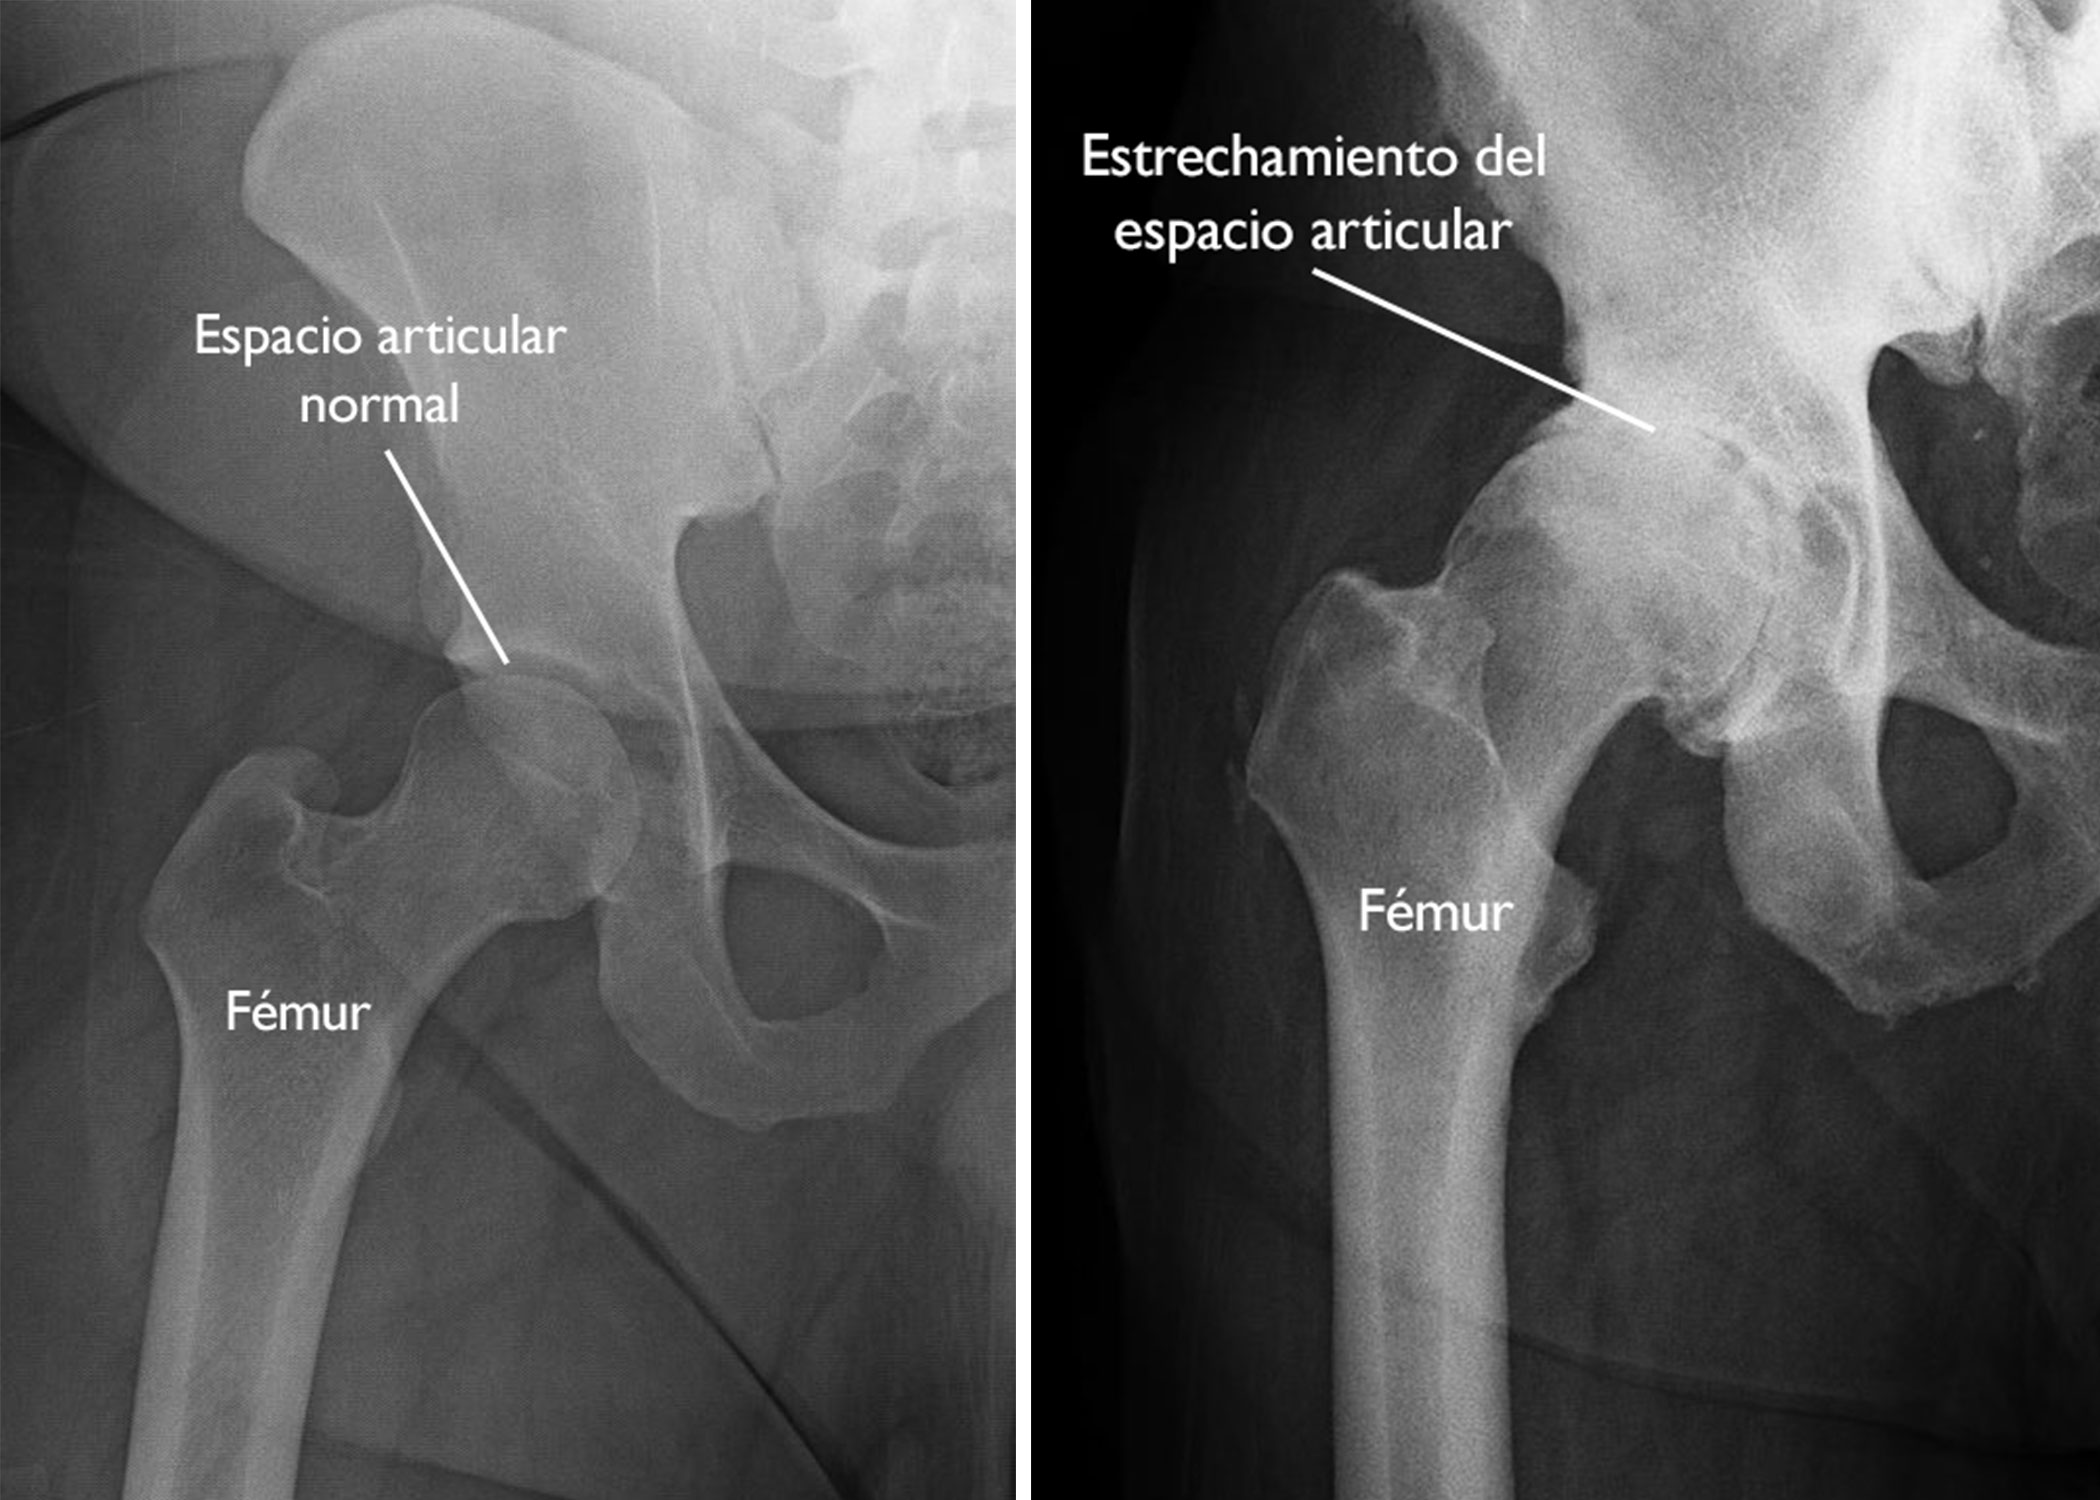

Radiografías. Con las radiografías se pueden obtener imágenes detalladas de las estructuras densas, como los huesos. Las radiografías de la cadera con artrosis pueden mostrar el estrechamiento del espacio articular y la formación de protuberancias óseas (osteofitos).

(Izquierda) En esta radiografía de una cadera normal, el espacio entre la bola y la cavidad es signo de un cartílago sano. (Derecha) Esta radiografía de una cadera con artrosis muestra la pérdida grave del espacio articular.